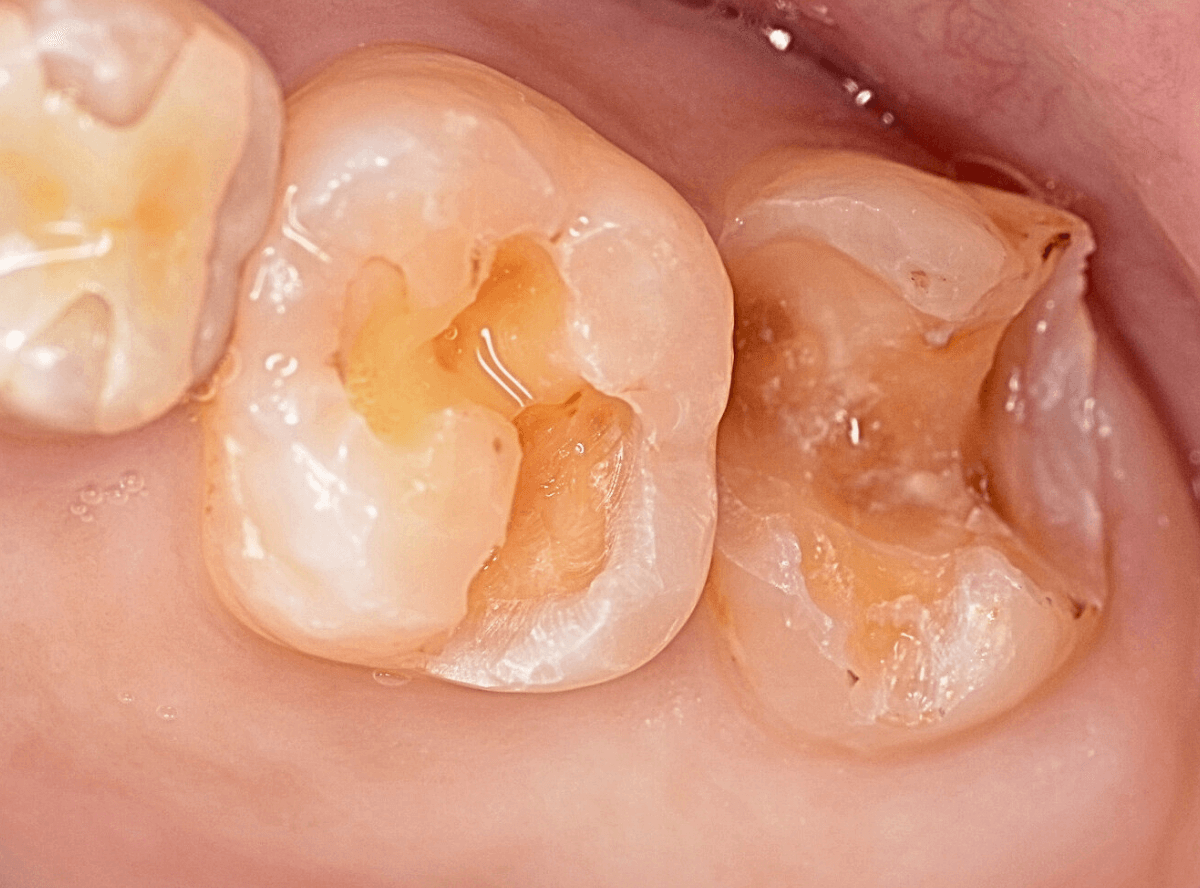

Case.14 インレーの下の歯肉まで広がった虫歯

「下の奥歯が噛むと痛む」という症状で来院された患者さんのケースです。

お口の中の状態を確認すると、奥歯の端に穴が開いているのが見えます。

ここかな?

レントゲン写真で確認します。